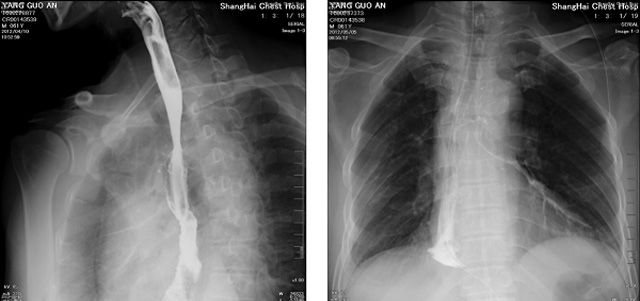

DR設(shè)備在2020年的新冠疫情中,加速了市場(chǎng)調(diào)整。以醫(yī)院為主的向二三級(jí)市場(chǎng)轉(zhuǎn)變。特別是小巧靈活的移動(dòng)DR設(shè)計(jì),填補(bǔ)CT和磁共振不能三維檢查的缺點(diǎn),滿足內(nèi)科外科特別是骨科的影像診斷需求。還有懸吊DR設(shè)備CT斷層射線系統(tǒng)。使用錐束成像技術(shù)對(duì)整個(gè)脊柱和整個(gè)下肢進(jìn)行了體積三維掃描。無(wú)需使用對(duì)比劑,即可使用X射線呼吸功能標(biāo)測(cè)來(lái)模擬模擬氣流和血流,以評(píng)估患者的肺動(dòng)脈血栓。

數(shù)字化X線攝影依然是患者初篩的關(guān)鍵一環(huán)。靜態(tài)DR限制于探測(cè)器平臺(tái)。只能進(jìn)行簡(jiǎn)單普通的數(shù)字化影像檢查。胸部的疾病沒(méi)辦法篩查出微小的病灶。這樣導(dǎo)致DR慢慢的被CT跟磁共振代替。這樣造成了原來(lái)配套的數(shù)字化影像DR設(shè)備的 閑置。所以DR需要跟CT融合擴(kuò)大DR的檢查使用場(chǎng)景。為DR提高更多的市場(chǎng)價(jià)值。X射線技術(shù)的原始形式和面向未來(lái)的可能性打破了CT成像和DR成像掃描技術(shù)之間的限制。融合成像趨勢(shì)更加明顯,多峰成像趨勢(shì)發(fā)展更加迅速。